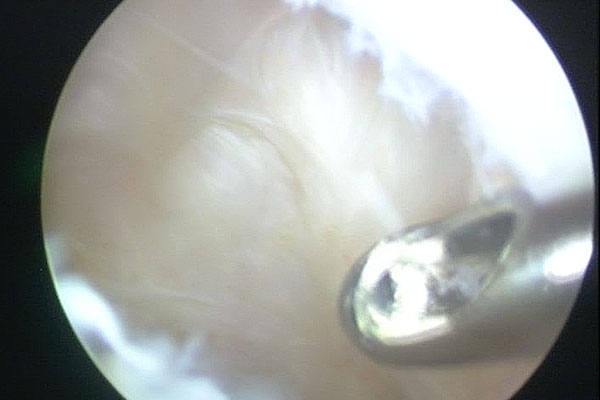

Arthroscopic Management of Baker's CYST